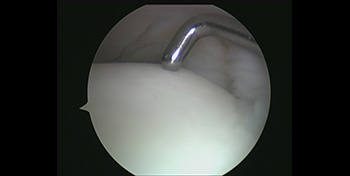

- Arthroscopy – Instead of having to open up the ankle joint to perform fusion surgery, the same can be accomplished with the use of Arthroscopy (key hole surgery) leading to faster recovery.

- Healthy vs Damaged cartilage – Arthroscopic view of healthy ankle cartilage on the right and damaged ankle joint on the left.